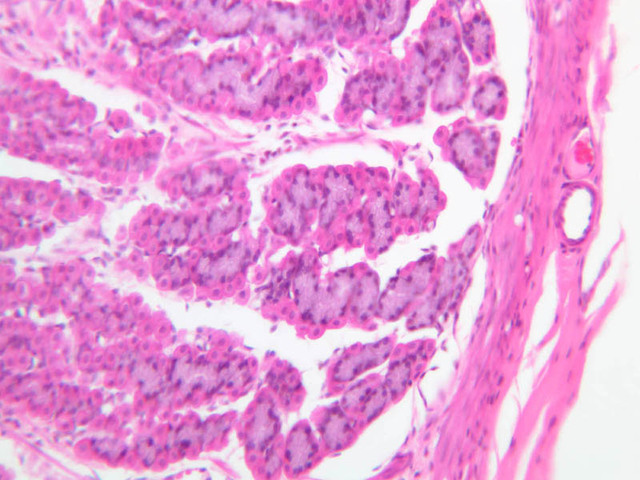

Examine slide B-4 (H&E [2.5x-labeled, 10x, 20x, 40x-labeled]) or B-5 (H&E [10x, 20x, 40x] [40x]) under the intermediate and high-dry objectives of your microscope. Mucous-secreting simple columnar cells, known as mucous surface cells, line the gastric lumen and the periodic deep depressions, known as gastric pits. The mucous surface cells differ from goblet cells both in their appearance and in the type of mucous they secrete. In H&E preparations they have a rather clear cytoplasm, but do not exhibit the sort of well-defined, unstained vacuoles that are typical of goblet cells. By contrast, in the PAS-stained section of slide B-6 (PAS [2.5x, 10x, 20x-labeled, 40x]) they stand out dramatically by virtue of their magenta-colored secretory product. As a rule, several glands extend from each gastric pit to the muscularis mucosae, largely obscuring the lamina propria. Small slips of smooth muscle that extend from the muscularis mucosae towards the luminal surface are presumed to be involved in expressing the glandular secretions.

The glands of the stomach exhibit regional variations in size, form, and cellular composition. The glands of the cardia (slide B-1) and pylorus (slide B-9) are coiled, often branched tubules that that are associated with very deep gastric pits and consist almost entirely of mucous-secreting cells. In the gastric fundus (slide B-4, H&E [2.5x, 10x, 20x, 40x] [10x, 20x, 40x-labeled] [40x]) and corpus (slides B-5, H&E [2.5x, 10x, 20x, 40x] [10x, 20x, 40x] [40x] & B-6, PAS [2.5x, 10x, 20x, 40x]), the glands are relatively straight and are known as fundic glands or gastric glands; they are made up of mucous neck cells, chief cells, parietal cells, and APUD cells. The lumina of fundic glands are much less evident than are those of cardiac and pyloric glands. Study slides B-4, 5 & 6 to familiarize yourself with the cell types found in fundic glands.

As their name suggests, mucous neck cells are most numerous just proximal to the junction of gastric gland and gastric pit. In H&E-stained sections, these cells, like others which secrete mucous (e.g., goblet cells), tend to stain poorly on account of the loss of their secretory product during histological processing. However, in the section on slide B-6, which has been stained by the PAS technique, they are very easy to identify (bright pink). You should study the distribution of mucous neck cells in this slide and then attempt to identify them in H&E preparations by looking at corresponding regions in slide B-4 or B-5. What functions are served by the mucous-secreting cells of the gastric mucosa?

The chief or zymogenic cells have a rather granular, basophilic cytoplasm and produce pepsinogen, which, upon encountering the acidic gastric juice, is converted into the proteolytic enzyme pepsin. As the name suggests, the chief cells are usually the most numerous cell type in the glands of the fundic region.

The parietal cells are large and have conspicuously acidophilic cytoplasm. They are the source of both gastric HCl. and intrinsic factor, which is necessary for uptake of vitamin B12 in the ileum. The fine structure of parietal cells shows that their cytoplasm is filled with a very large number of surface invaginations or secretory canaliculi, which, in turn, are covered with microvilli. It is apparently this elaboration of surface area that allows parietal cells to secrete large amounts of HCl. Why are parietal cells eosinophilic?